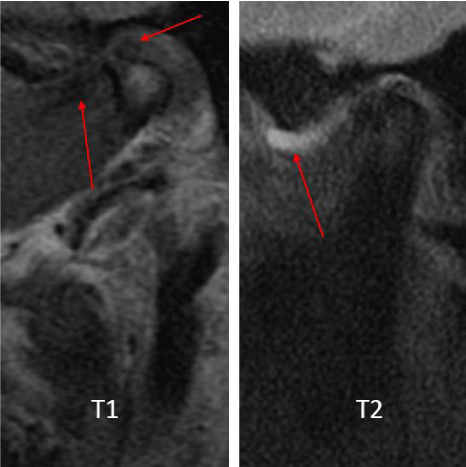

A 53-year-old male presented with a complicated musculoskeletal history consisting of head and neck dystonia and suprahyoid musculature spasms resulting in painful recurrent mandibular subluxation. Examination revealed a mouth-opening of 60 mm with ongoing subluxation due to muscle spasms. The CT scan of the left side suggested severe degenerative changes with multiple rounded erosive foci and a hazy periosteal reaction at the skull base (Figure 6). The T1 weighted MRI showed low signal intensity in the condylar bone marrow on the left. The disc was not visualized and there was no evidence of intra-articular mass (Figure 7). Diagnostic arthroscopy of the left showed a large central perforation of the disc with remarkable nodular synovitis. Synovial biopsy, synovectomy and debridement were performed (Figure 8). Histologic examination showed PVNS (Figure 9). Additional surgical treatment for the dislocation and the degenerative changes of the TMJ was deferred until further control of the muscular dystonia was achieved.

A 72-year-old female presented with left-sided jaw pain. Examination revealed tenderness over the left masseter, a mouth-opening of 35 mm and bilateral joint noises. Her left side had direct and indirect loading. The CT scan showed degenerative changes of the left condyle with a 2x2 mm subchondral cyst (Figure 10). The MRI revealed a degenerative left condyle with a deformed disc. The T2 weighted imaging showed a superior joint space effusion (Figure 11). Diagnostic arthroscopy showed retrodiscal synovitis, chondromalacia and a perforated disc. There were crystal-like structures within the synovium antero-medially. Synovial biopsy, debridement and partial synovectomy were performed (Figure 12). Histologic examination showed proliferative synovitis with calcium pyrophosphate deposition (Figure 13). The patient was referred for rheumatological management of CPPD but no treatment was initiated due to symptom resolution. On her 6-month follow-up her pain had resolved; she was maintaining a regular diet and her mouth-opening had become 45 mm with no joint loading.